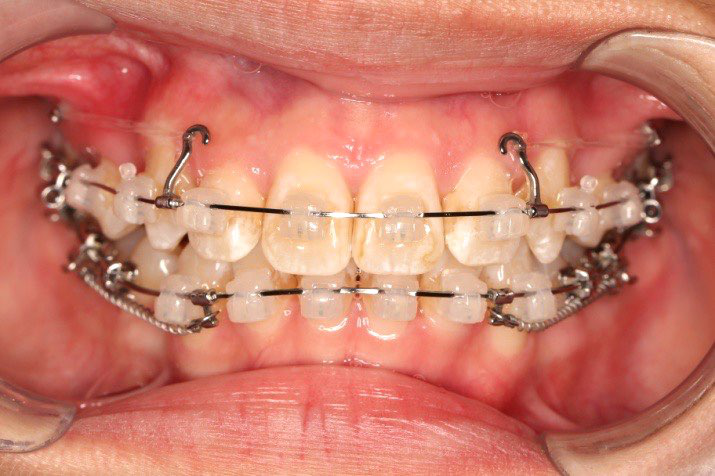

2018.11.14  术后磨牙尖牙I类关系,中线齐,覆合,覆盖正常

2018.11.14  术后侧面改善明显,露龈笑改善明显,笑弧笑线协调,颏部肌肉紧张度明显改善

2018.5.25  (19个月)拆TPA,16、26粘tube 上颌0.14*25cu-niti  下颌0.018*25niti2018.7.23  上颌 0.017*25TMA,下颌0.017*25ss43压低曲,双侧后牙垂直牵引

2018.09.29  15、43、16、17、11、21重粘,上0.016*25cu-niti 下0.018niti 上连扎